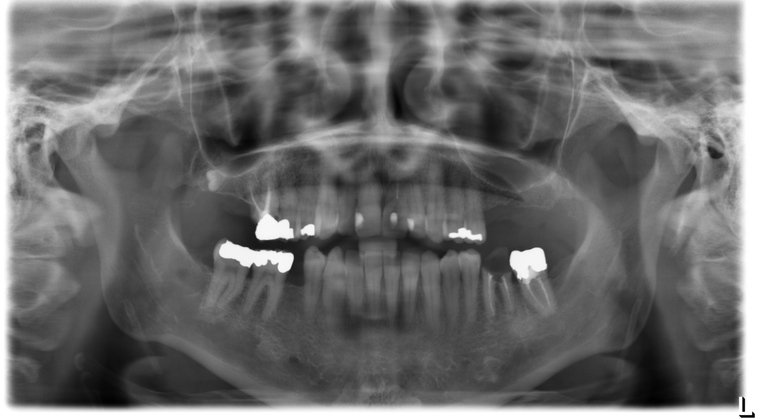

Ein Tätigkeitsschwerpunkt unserer Praxis in Salzburg ist die Implantologie. Wenn ein Zahn fehlt oder entfernt werden muss, sollte immer die Möglichkeit der Implantation im Vordergrund stehen. Ein Implantat verhält sich von den Eigenschaften genau so wie ein natürlicher Zahn. Egal ob nur ein einzelner Zahn vom Zahnarzt ersetzt werden muss oder ein ganzer Kiefer mit festsitzendem Zahnersatz versorgt werden soll, wir finden für Sie eine Möglichkeit, auch wenn die Voraussetzungen ausweglos erscheinen. Wenn möglich versorgen wir unsere Patienten mit Keramikimplantaten. Diese sind immun-neutral und können sehr oft direkt bei der Zahnextraktion eingesetzt werden. Für unsere Patienten ist daher meist nur ein operativer Eingriff notwendig!

- 3D-Röntgentechnik, 3D-Implantatplanung und virtuelle Implantation

- Knochenaufbau mit Ersatz- und/oder Eigenknochen